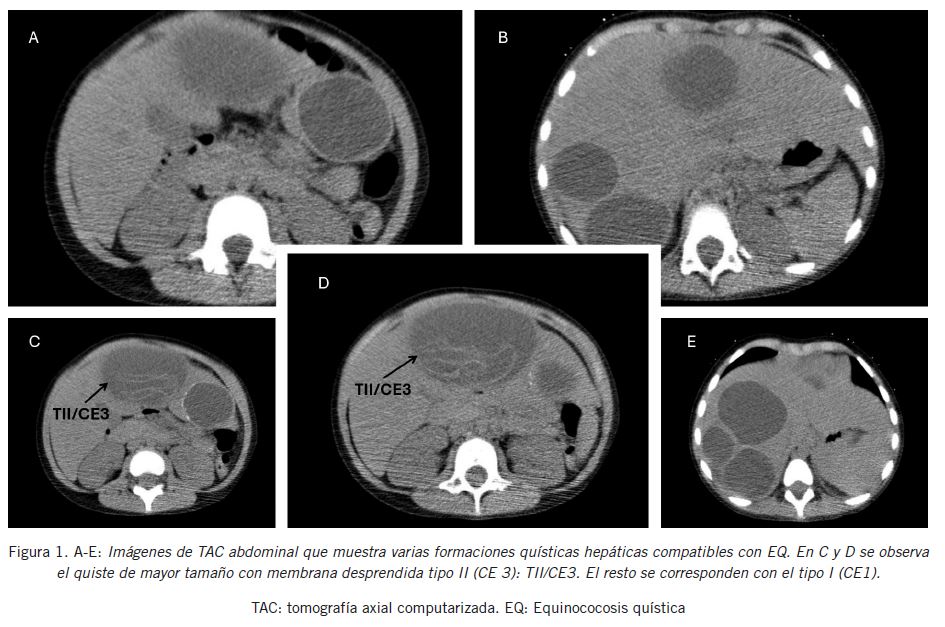

Se presenta un caso pediátrico de EQ complicada, con múltiples quistes en hígado, en una paciente de tres años de edad habitante de una localidad urbana del sudoeste bonaerense que presentó fiebre, síntomas gastrointestinales: dolor abdominal, náuseas y vómitos y una masa palpable en epigastrio con hepatomegalia. Se indicó ecografía abdominal que mostró numerosos quistes hidatídicos en ambos lóbulos hepáticos y líquido en fondo de saco y pelvis menor que se interpretó como posible rotura de un quiste y siembra hidatídica peritoneal. La radiografía de tórax fue normal. La paciente fue derivada al servicio de pediatría del Hospital Interzonal General de Agudos (H.I.G.A.) “Dr. José Penna” de Bahía Blanca. Se realizó una tomografía axial computada (TAC) multislices de abdomen y pelvis que reveló nueve quistes hidatídicos de diversos tamaños en el parénquima hepático (Fig. 1). El mayor midió 88 x 76 x 63 mm, ocupaba aproximadamente el 50% del diámetro del lóbulo hepático izquierdo y se clasificó como de tipo II (CE3): hialino, anecoico, con membrana laminar «desprendida» o «plegada», signo de la serpiente, quistes transicionales, generalmente fértiles (7) (Fig. 1 C y D). El quiste menor midió 18 x 16 x 15 mm y éste y el resto de los quistes se correspondieron con el tipo I (CE1): hialino, contenido líquido, anecoico, con membrana laminar visible, con o sin signo del nevado. Estos quistes son activos, generalmente fértiles y contienen protoescólex viables (7). Se inició tratamiento con albendazol y se realizó la cirugía una semana posterior a su ingreso al hospital con un diagnóstico preoperatorio de EQ hepática gigante. Se aplicó laparotomía exploradora con segmentectomía hepática izquierda, periquistectomía radical derecha, lobectomía hepática derecha y colecistectomía retrógrada.